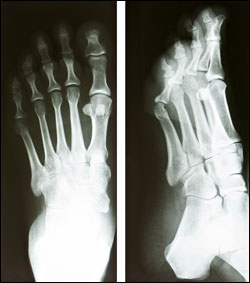

It’s possible to injure bones in the foot or ankle without knowing it. What may seem like a sprain at the time may actually be a fracture. See a podiatrist at the first onset of ankle pain. The sooner you start treatment, the better your chance of preventing long-term problems like instability, and the sooner you can get back in the game.